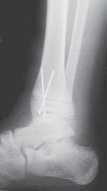

19. Many Salter type II fractures can be successfully stabilized with two 0.062-inch smooth Kirschner wires.

1. The wires are placed from distal to proximal, from the anteromedial malleolus and from the anterolateral corner of the tibial epiphysis (

TECH FIG 2

).

A B C DTECH FIG 2•

Treatment of Salter-Harris type II supination–external rotation (SER) type of fracture with interposed periosteum.

A,B.

Radiographs demonstrate a Salter-Harris type II SER type of fracture gapped anteriorly.

C.

Periosteum (shown in red) is often interposed anteriorly in SER-type Salter-Harris II fractures, which prevents closed reduction.

D.

This periosteum must be carefully extracted from the physeal fracture to obtain anatomic reduction and decrease the chance of premature physeal closure.

(continued)

TECHNIQUES E F G HTECH FIG 2•

(continued)_E,F. Open reduction was obtained after failed closed reduction due to interposed periosteum in the physeal fracture. Then the fracture was stabilized with two crossed Kirschner wires placed percutaneously. G,H. At 1 year postoperatively the distal tibial physis appears open. The _red arrows

mark the Harris growth line, which is parallel with the physis, demonstrating symmetric growth after injury. This further supports that the tibial physis is open.